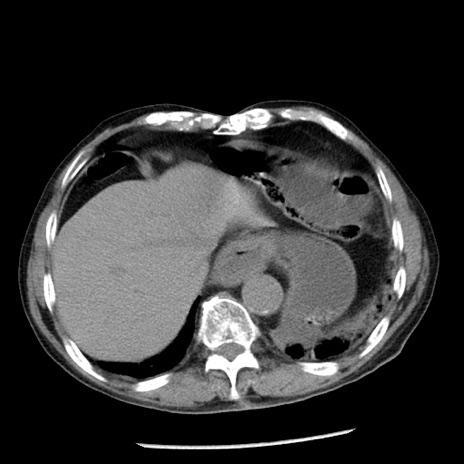

症例26(横断像)

【症例】80歳代男性

【主訴】嘔吐

【現病歴】昨晩2回嘔吐あり、今朝になっても嘔吐あり。来院。

【既往歴】胃潰瘍

【身体所見】意識清明、BT 37.6℃、BP 166/95mmHg、HR 100bpm、SpO2 97%、腹部:平坦・軟、腸蠕動音聴取良好、圧痛なし。

【データ】WBC 21900、CRP 1.46